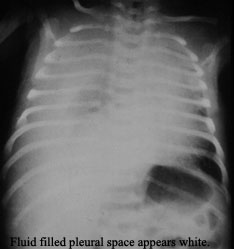

A pleural effusion composed of lymphatic fluid due to disruption of the thoracic duct.